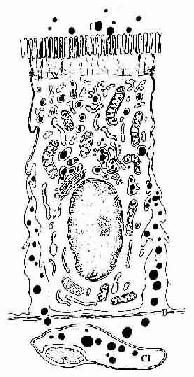

(1)吸收细胞(absorptive cell):最多,呈高柱状,核椭圆形,位于细胞基部。绒毛表面的吸收细胞游离面在光镜下可见明显的纹状缘,电镜观察表明它是由密集而规则排列的微绒毛构成(图12-16)。每个吸收细胞约有微绒毛1000根,每根长1~1.4μm ,粗约80nm ,使细胞游离面面积扩大约20倍。小肠腺的吸收细胞的微绒毛较少而短,故纹状缘薄。微绒毛表面尚有一层厚0.1~0.5μm的细胞衣,它是吸收细胞产生的糖蛋白,内有参与消化碳水化合物和蛋白质的双糖酶和肽酶,并吸附有胰蛋白酶、胰淀粉酶等,故细胞衣是消化吸收的重要部位。微绒毛内有纵行微丝束,它们下延汇入细胞顶部的终末网(图12-17)。吸收细胞胞质内有丰富的线粒体和滑面内质网。滑面内质网膜含有的酶可将细胞吸收的甘油-酯与脂肪酸合成甘油三酯,后者与胆固醇、磷脂及β-脂蛋白结合后,于高尔基复合体形成乳糜微粒,然后在细胞侧面释出,这是脂肪吸收与转运的方式。相邻细胞顶部之间有紧密连接、中间连接等构成的连接复合体,可阻止肠腔内物质由细胞间隙进入组织,保证选择性吸收的进行(图12-17)。

图12-16 小鼠小肠吸收细胞电镜像 ×9900

Mv微绒毛,N细胞核